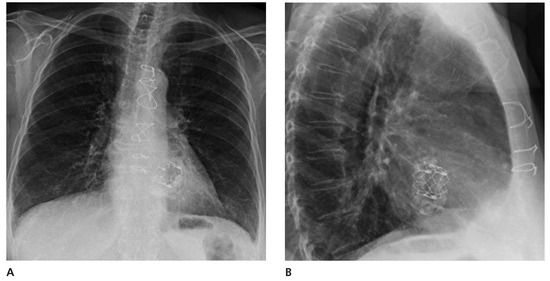

Worldwide First Surgical Implantation of a Transcatheter Valved Stent in Mitral Position

Case report